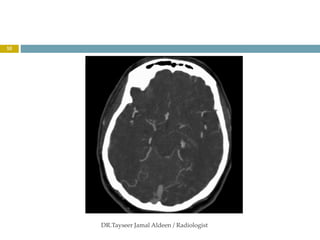

This document discusses several types of orbital vascular lesions. It describes venous lymphatic malformations, which may be present at birth and enlarge slowly, sometimes hemorrhaging. Orbital venous lymphatic malformations are isolated from normal orbital vasculature. CT scans show they are heterogeneously hyperattenuating and enhance minimally. The document also discusses ophthalmic artery aneurysms, which can compress the artery or optic nerve if over 3mm. Choroidal hemangiomas are congenital vascular hamartomas that appear as intensely enhancing lentiform masses on CT scans.